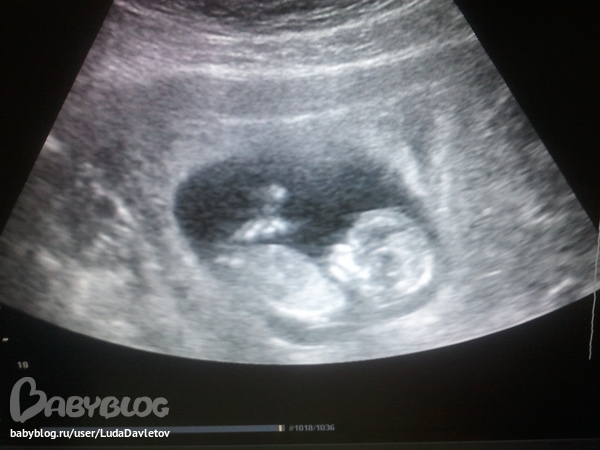

Наше первое УЗИ!

Вчера ходила на узи! Запись была на 9, как путная захожу в свое время, ложусь, начинают обследование и уже вижу на экране какие то милые очертания, но ничего не могу понять. И мне говорят "Идите походите, плод не готов к обследования, лежит не так!". Вот дуаю вреднуля!) Но все ранво счасливая до безумия, потому, что врач видимо включила, что то типа кардиограммы и видно было, что сердечко бьется!)

Хожу значит, мысленно уговарияваю повернуться, что бы все посмотрели. В итоге зашла только в 10 еще раз. Но тут уж не подвел , все показал:

КТР 60 мм, Кости носа 2,36 мм, ЧСС 158, ТВП 1,6 мм, Преимущественная локализация хориона передняя. Соотвтсвуем сроку 12,4 недели, как и по месячным.

Все показали мне, пальчики посчитали, так классно. А главное прям видно как в теле сердечко бьется! Очень рада!!!